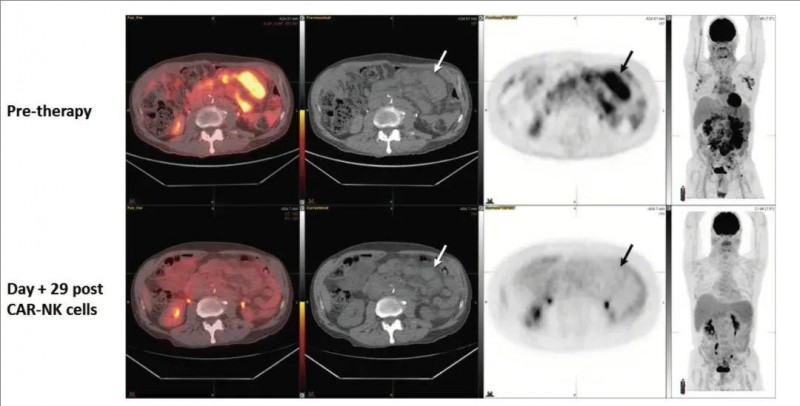

尤其值得关注的是,其中一位发生Richter转化的慢性淋巴细胞白血病(CLL)患者(患者 5),其高级别淋巴瘤也实现了完全缓解(CR)(详见下图)。

▼该患者CAR-NK细胞输注前后的FDG PET-CT、PET-CT对比

▲图源“N Engl J Med”,版权归原作者所有,如无意中侵犯了知识产权,请联系我们删除